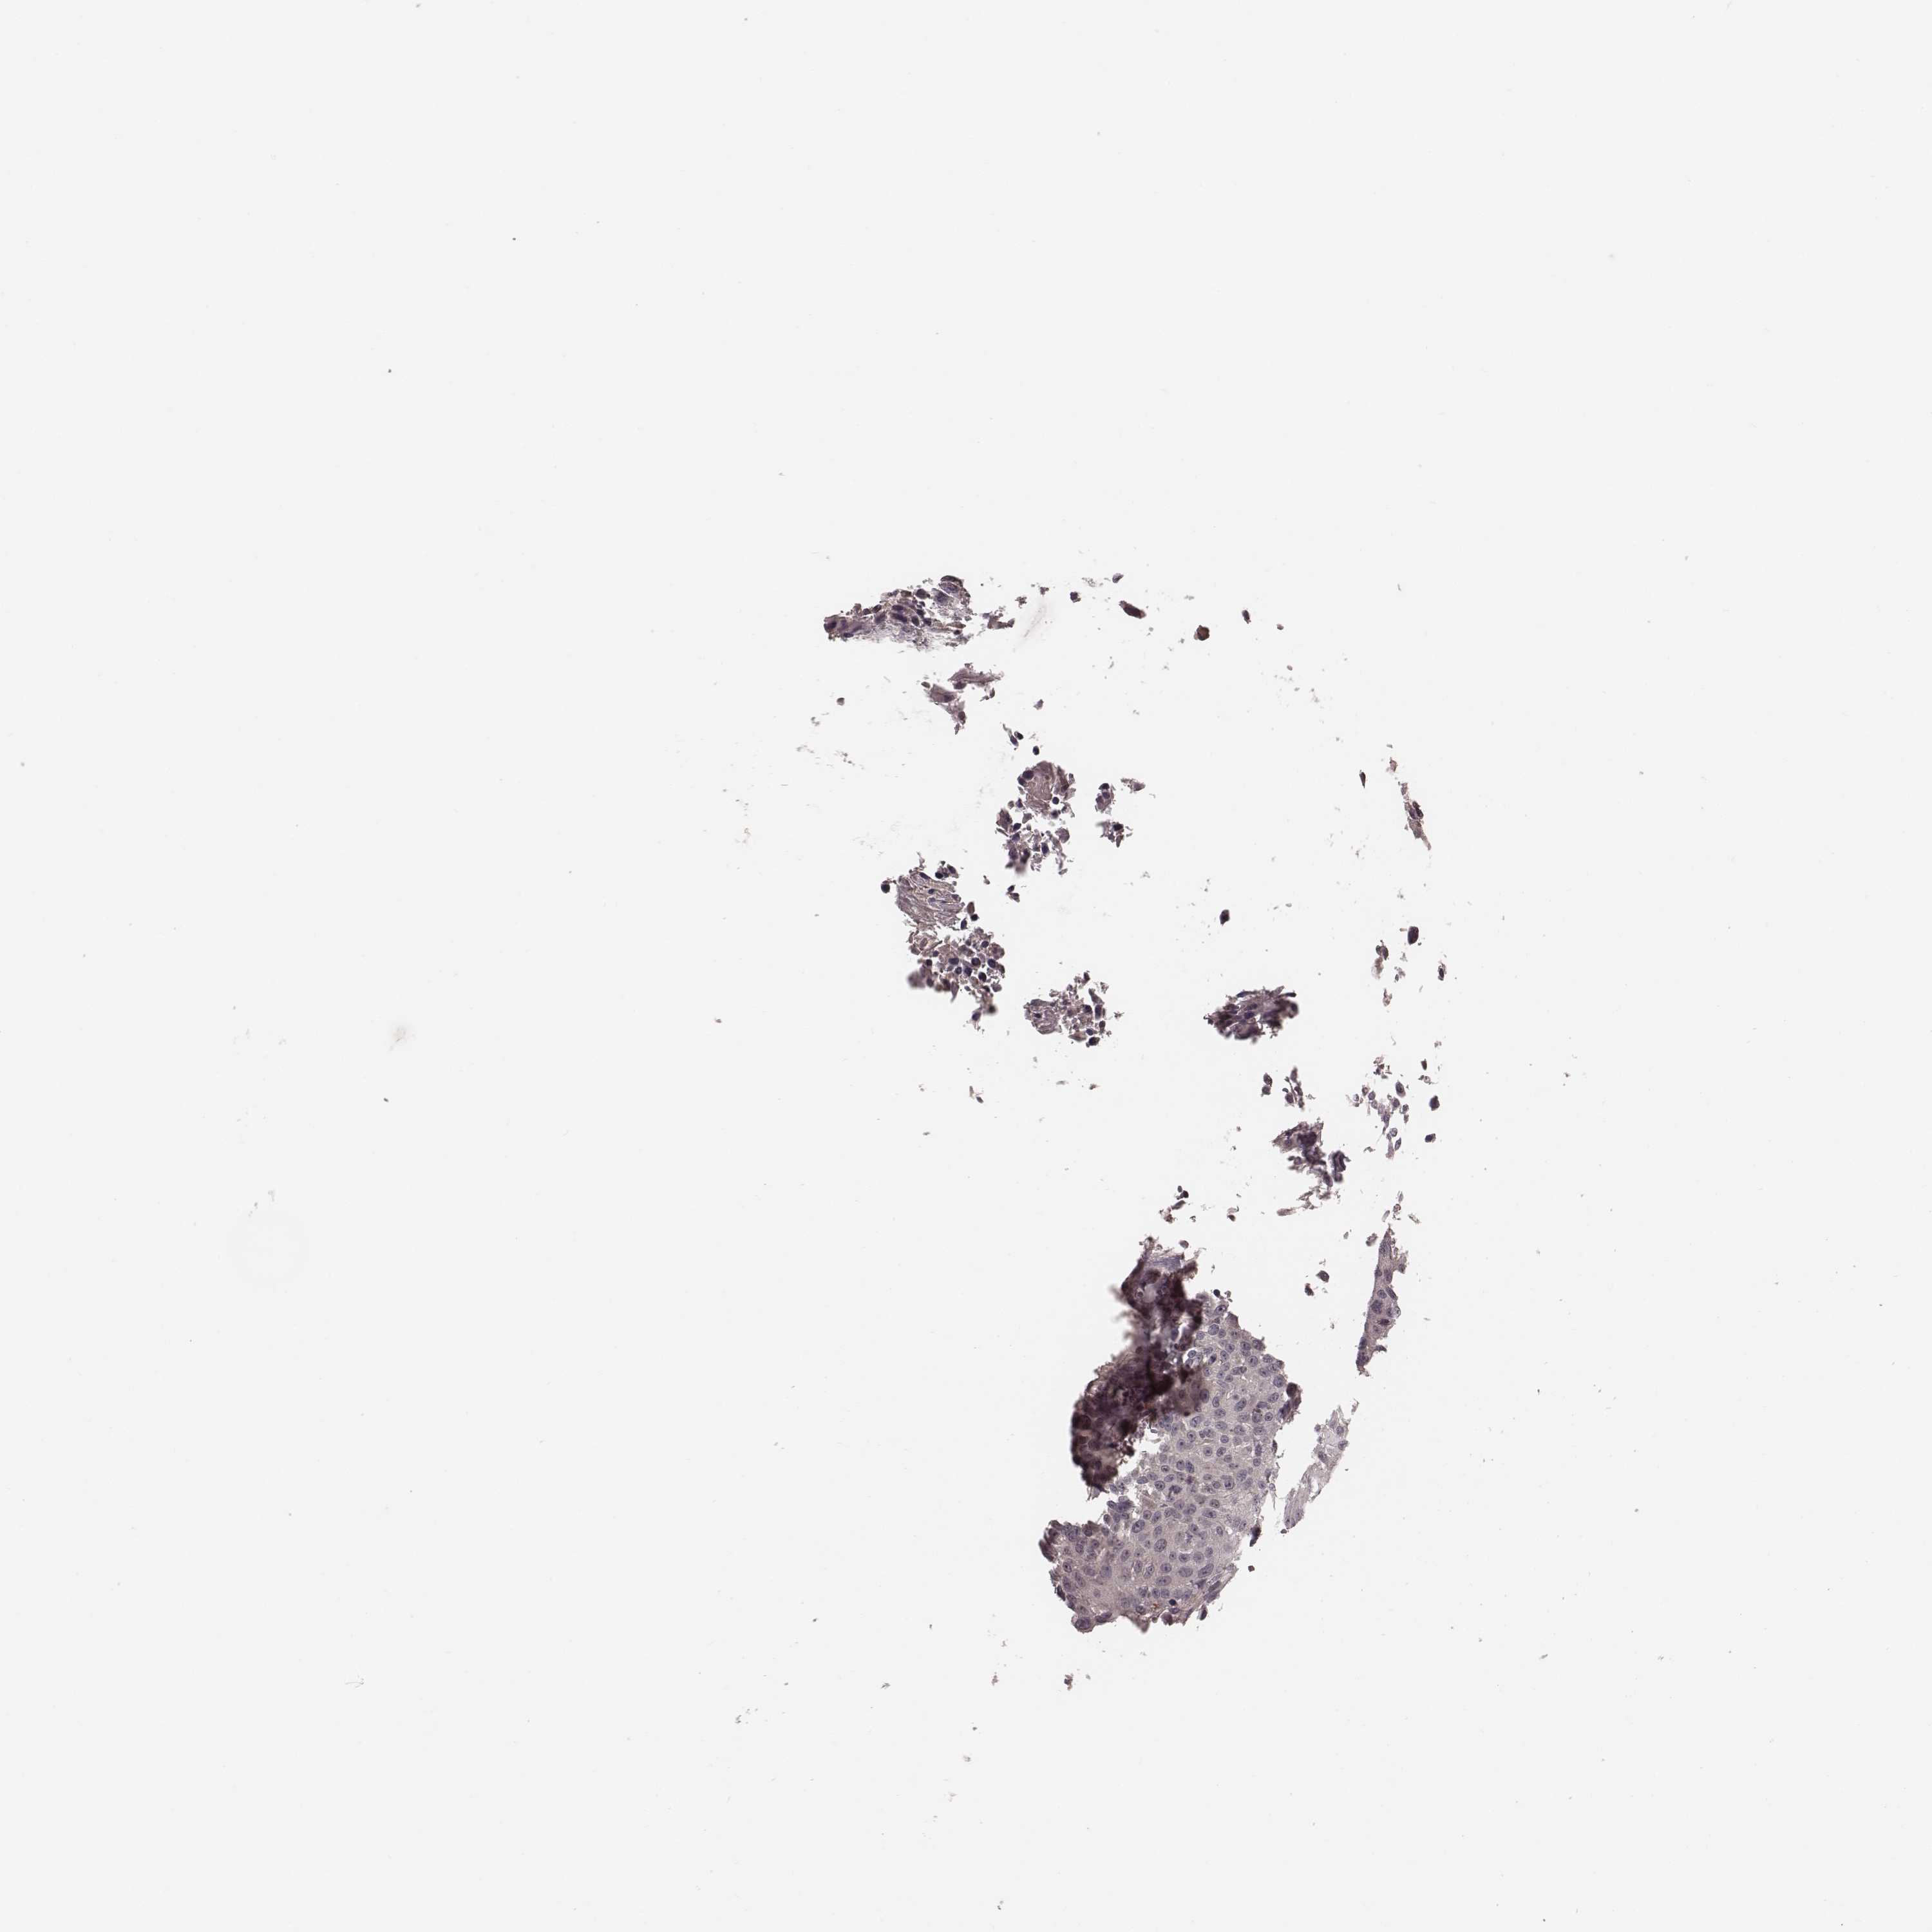

UROTHELIAL CANCER - Protein expressioni

A mouse-over function shows sample information and annotation data. Click on an image to view it in a full screen mode. Samples can be filtered based on level of antibody staining by selecting one or several of the following categories: high, medium, low and not detected. The assay and annotation is described here.

Note that samples used for immunohistochemistry by the Human Protein Atlas do not correspond to samples in the TCGA dataset.

Antibody stainingi

Antibody staining in the annotated cell types in the current human tissue is reported as not detected, low, medium, or high, based on conventional immunohistochemistry profiling in selected tissues. This score is based on the combination of the staining intensity and fraction of stained cells.

Each image is clickable and will lead to virtual microscopy that enables deeper exploration of all samples and also displays staining intensity scores, fraction scores and subcellular localization as well as patient and tissue information for each sample.

Antibody CAB010304

Staining

Urothelial carcinoma, High grade

Urothelial carcinoma, NOS

Urothelial carcinoma, Low grade